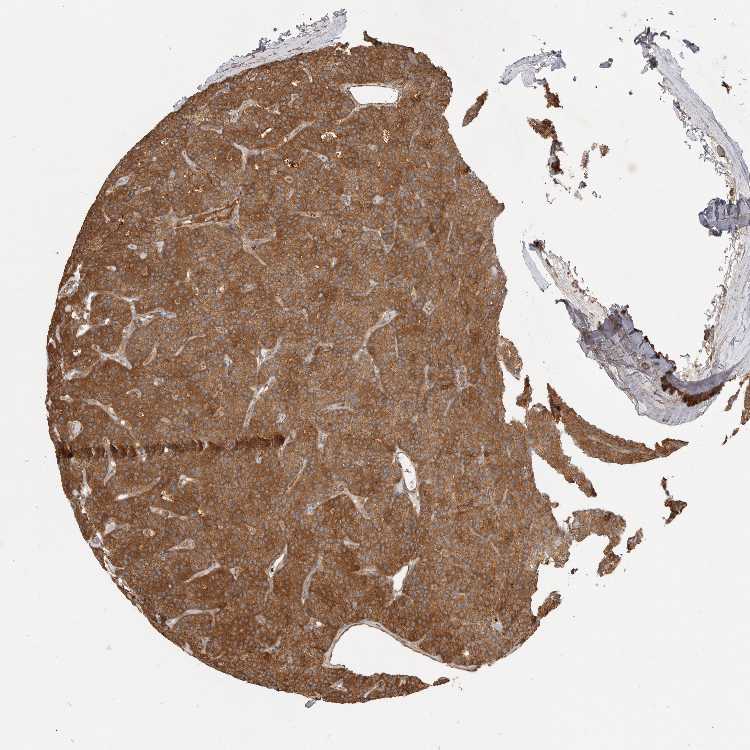

PARATHYROID GLAND - Antibody stainingi

Antibody staining in the annotated cell types in the current human tissue is reported as not detected, low, medium, or high, based on conventional immunohistochemistry profiling in selected tissues. This score is based on the combination of the staining intensity and fraction of stained cells.

Each image is clickable and will lead to virtual microscopy that enables deeper exploration of all samples and also displays staining intensity scores, fraction scores and subcellular localization as well as patient and tissue information for each sample.

Antibody HPA026945

Glandular cells High